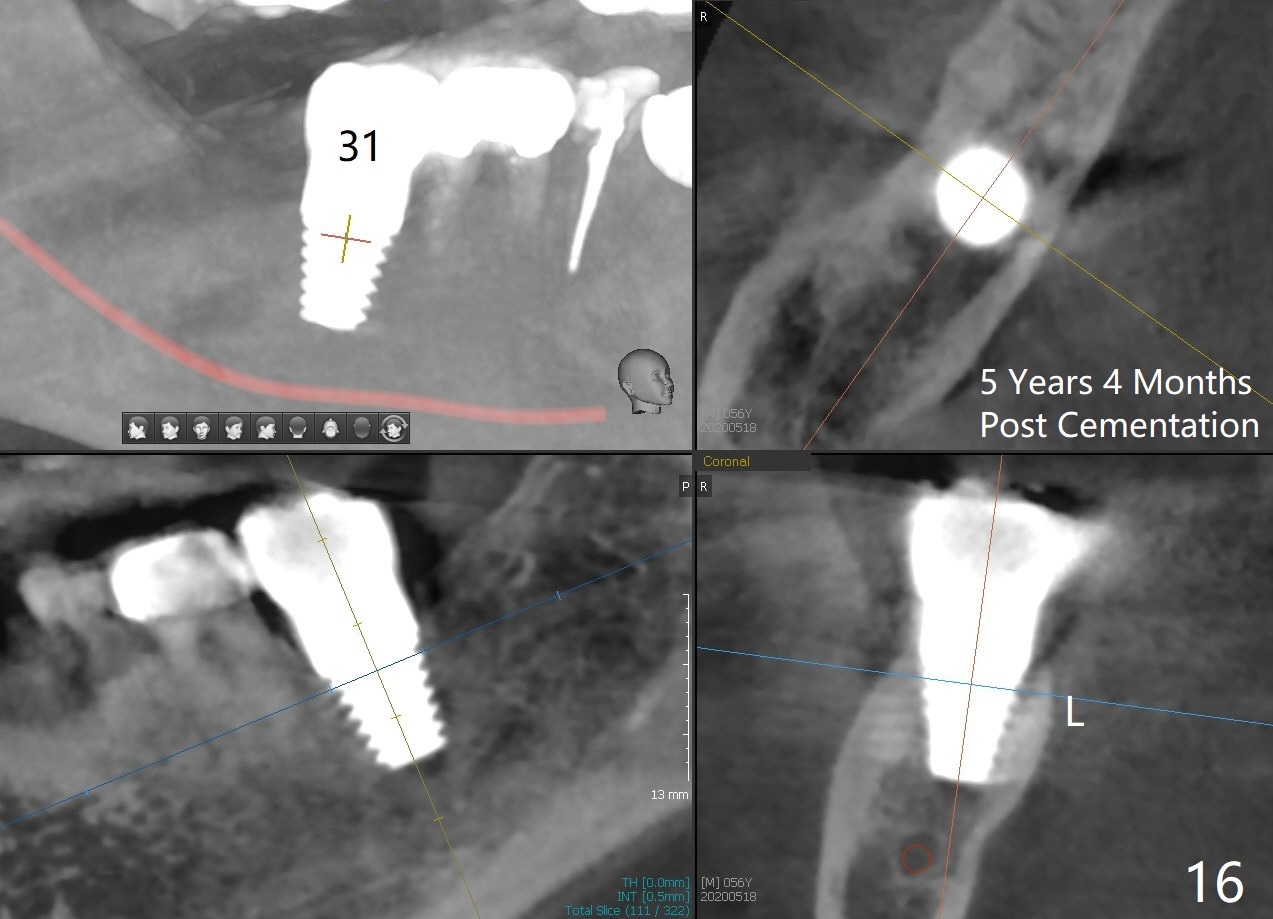

The patient returns for final restoration 5.5 months postop; it appears that the distal gap has disappeared (Fig.13 *). There is no bone loss 26 months post cementation (Fig.14). The lamina dura-like dense bone forms coronally 3 years 4 months post cementation (Fig.15 *). The 8 mm implant remains buried in the bone 5 years 4 months post cementation (Fig.16).